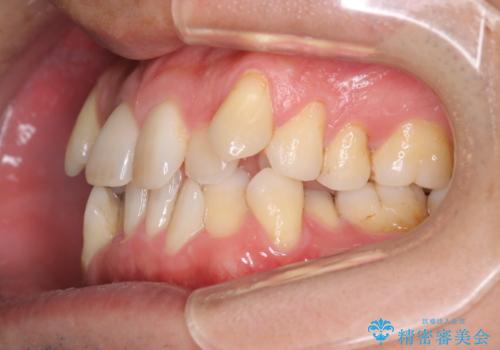

- 治療計画

叢生量が大きいため、上下顎両側4番を抜歯しました。矯正治療による歯肉退縮の著しい悪化もなく、主訴であるガタつきも改善できました。